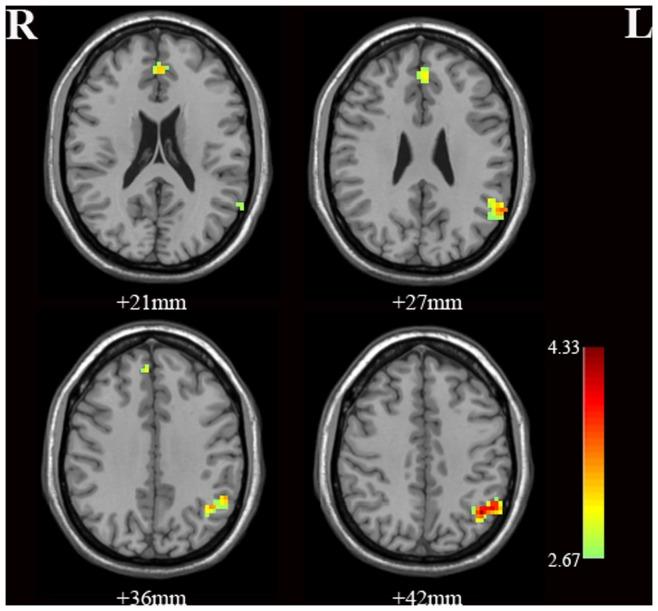

Our results revealed that bipolar depressed patients had increased ReHo in the left medial frontal gyrus and left inferior parietal lobe compared to healthy controls. No correlations were found between regional ReHo values and sex, age, and clinical features within the BD group.

我们的结果表明,与健康对照组相比,双相抑郁患者的左侧额内侧回和左侧顶下小叶的 ReHo 增加。BD 组中,区域 ReHo 值与性别、年龄和临床特征之间无相关性。